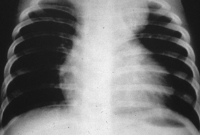

La causa más frecuente del síndrome de Horner en la infancia es la lesión traumática del plexo braquial durante el parto. Si no existe el antecedente traumático, hay que descartar el neuroblastoma que se manifiesta como tumoración mediastínica o cervical. El estudio inicial incluye una radiografía de tórax (Figura 16) y la determinación de catecolaminas en orina de 24 horas. Si la radiología es normal, debe valorarse una AngioRM cerebral, por la posibilidad de una malformación arteriovenosa.

Figura 16. Radiografía de tórax: Ensanchamiento del mediastino producido por un neuroblastoma